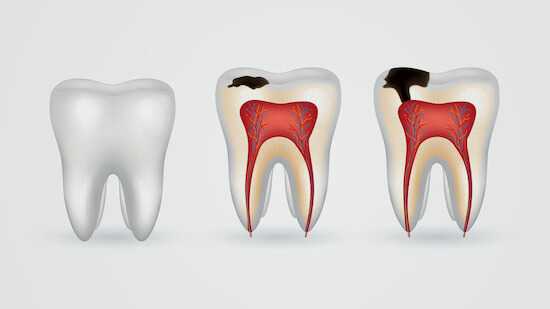

Кариес. Наиболее распространенная причина потемнения зубной эмали. Отличительной особенностью является изменение цвета одного зуба. В редких случаях темнеет несколько соседних зубов. Кариес может проявиться в виде пятна или кариозной полости. Если протекает пришеечная форма кариеса, то темнеют корни зубов (прикорневая зона).

Из-за повышенной проницаемости эмали под её поверхностью появляется очаг поражения (меловидное пятно) — признак деминерализации. В дальнейшем образуется кариозная полость [2] .

Деминерализации зубов может привести к образованию среднего и глубокого кариеса.

Средний кариес затрагивает эмаль и поверхностный слой дентина. При зондировании отмечается болезненность в области эмалево-дентинного соединения. Температурные раздражители вызывают боль, но она быстро проходит после устранения раздражающего фактора.

При глубоком кариесе поражение твёрдых тканей зуба обширнее. Патология затрагивает глубокие слои дентина. При зондировании отмечается болезненность по дну кариозной полости. Температурные раздражители вызывают резкую, сильную боль, но после устранения раздражающего фактора она быстро проходит.